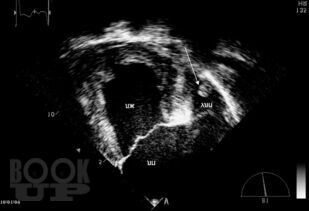

Книга посвящена одной из актуальных проблем кардиологии—тромбоэмболическим осложнениям у больных с аритмиями. Подробно обсуждаются молекулярные и генетические механизмы тромбообразования при аритмиях, клинические и инструментальные признаки внутрисердечных тромбов, а так же способы их визуализации. Приводятся данные о способах оценки риска тромбоэмболических осложнений и тактике антитромботической терапии в различных группах больных с аритмиями. Отдельно освещаются вопросы антитромботической терапии в сложных клинических ситуациях — при хирургических операциях, в случае обострения ИБС, при беременности, при проведении катетерной деструкции. Поводом для выхода второго издания книги послужило появление представителя нового класса антитромботических средств — дабигатрана этексилата, в связи с чем международное кардиологическое сообщество поменяло рекомендации по профилактике тромбоэмболических осложнений у больных с аритмиями. Для кардиологов (в том числе интервенционных), терапевтов, студентов медицинских вузов.